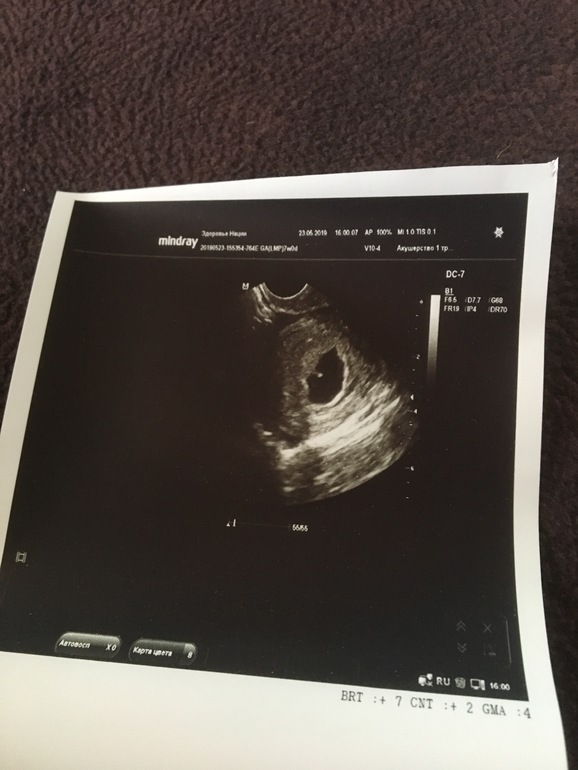

Наше первое УЗИ 😊

Сходили сегодня на первое УЗИ, всё хорошо)

Только я предполагала 7 полных недель, а оказалось 6 недель и 1 день, хорошо что сердечко уже услышали 😊

Ещё и матка оказалась с загибом, сложно было найти малыша